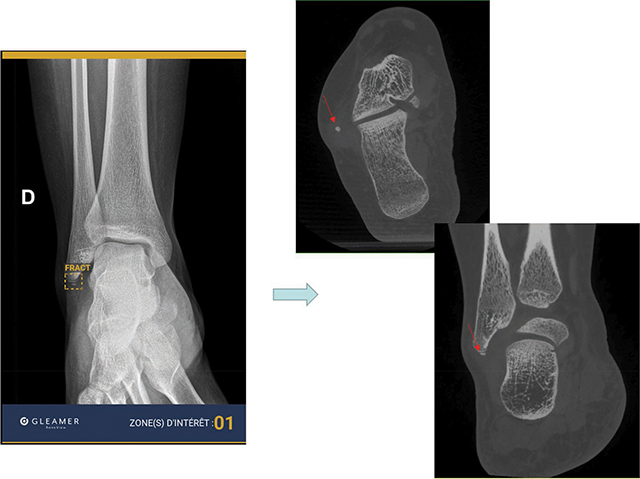

Objectives: The aims of this study were: (a) to evaluate the performance of an artificial intelligence (AI) software package (Boneview Trauma, Gleamer) for the detection of post-traumatic bone fractures in radiography as a standalone; (b) used by two radiologists (osteoarticular senior and junior); and (c) to determine to whom AI would be most helpful.

Materials and methods: Within 14 days of a trauma, 101 consecutive patients underwent radiographic examination of the upper or lower limbs. The definite diagnosis for identifying fractures was: (a) radio-clinical consensus between the radiologist on-call who analyzed the images and the orthopedist (Group 1); (b) Cone Beam computed tomography (CBCT) exploration of the area of interest, in case of doubts or absence of consensus (Group 2). Independently of this diagnosis for both groups, the radiographic images were separately analyzed by two radiologists (osteoarticular senior: SR; junior: JR) prior without, and thereafter with the results of AI.

Results: AI performed better than the radiologists in detecting common fractures (Group 1), but not subtle fractures (Group 2). In association with AI, both radiologists increased their overall performances in both groups, whereas this increase was significantly higher for the JR (p < 0.05).

Conclusion: AI is reliable for common radiographic fracture identification and is a useful learning tool for radiologists in training. However, the software's overall performance does not exceed that of an osteoarticular senior radiologist, particularly in case of subtle lesions.